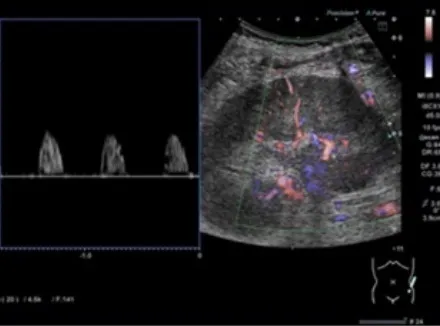

A ressonância magnética (abaixo) mostrou dilatação da veia testicular esquerda e da veia capsular renal. A tomografia computadorizada sem contraste revelou rim esquerdo aumentado, veia renal esquerda dilatada e infiltração perirrenal. Ultrassonografia Doppler mostrou fluxo sistólico isolado nas artérias interlobares, sugerindo congestão renal. Foi confirmado trombose da veia renal com êmbolo na junção com a veia testicular.

Achados de ressonância magnética sem contraste e ultrassonografia Doppler que sugerem trombose da veia renal. (A e B) Ressonância magnética mostrando aumento da (A) veia testicular esquerda e da (B) veia capsular renal. (C) Ultrassonografia Doppler da artéria interlobar mostrando fluxo sanguíneo apenas na fase sistólica.